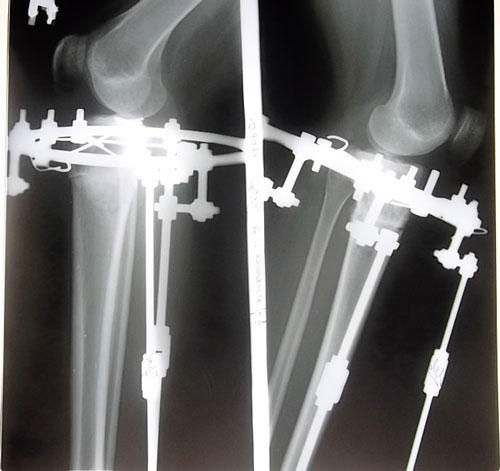

рентген перед снятием аппаратов.

Вложения

SAM_6526.JPG

SAM_6525.JPG

Дата операции 04.06.2013г.

Дата снятия аппаратов 22.08.2013г.

Срок лечения 77 дней.